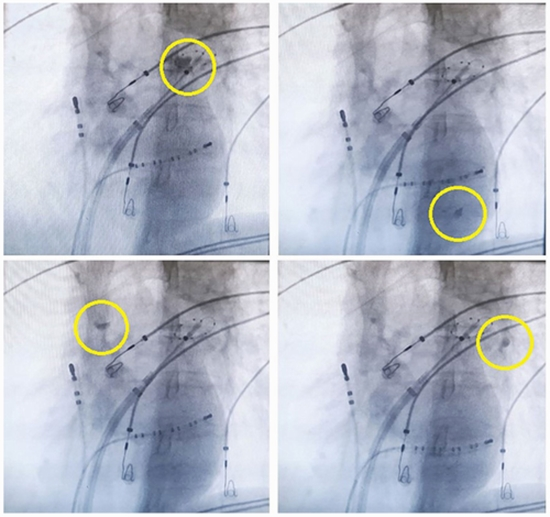

پژوهشگران در یک مورد بالینی نادر، تشکیل و ماندگاری کلاهک یخی رنگی بر روی بادکنک کرایوبالون را گزارش کردند که پس از آزاد شدن بادکنک ممکن است وارد جریان خون شود. این پدیده گرچه نادر است، اثری منفی روی بیمار نداشت و نیاز به شناخت بیشتر برای جلوگیری از عوارض احتمالی دارد. مطالعه نشان می‌دهد که با تنظیمات دقیق دستگاه، این عارضه به حداقل می‌رسد و درمان با ایمنی بالایی قابل انجام است.

مقاله گزارشی از یک مورد بیمار ۷۰ ساله است که با وجود مصرف داروهای ضد آریتمی، دچار حملات آریتمی بوده و برای درمان تحت عمل ایزولهسازی وریدهای ریوی (PVI) با کرایوبالون (Cryoballoon) قرار گرفت. در طی پروسه، کلاهک یخی حامل ماده رنگی روی بادکنک شکل گرفت که ابتدا در ورید ریوی چپ فوقانی به جریان خون وارد و به سمت قلب و آئورت حرکت کرد، اما خوشبختانه بیمار بدون مشکل از این اتفاق گذشت. در ورید ریوی راست فوقانی نیز کلاهک یخی شکل گرفت اما پس از چند ثانیه به صورت طبیعی ذوب شد و در گردش خون باقی نماند.

• در طول انجام این درمان، ممکن است قطعات یخی کوچک همراه با ماده رنگی روی بادکنک شکل بگیرد. اگر بادکنک زودتر از حل شدن این قطعات یخی باز شود، ممکن است این قطعات وارد خون شده و به سایر اندامها منتقل شوند ولی تاکنون عوارض جدی گزارش نشده است.